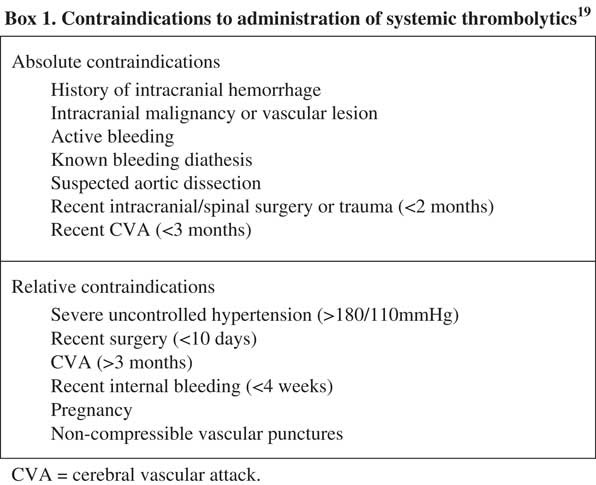

Systemic thrombolysis is the standard of care in patients who present with high-risk PE, barring any contraindications (Figure 4).Reference Konstantinides, Torbicki and Agnelli 5 , Reference Jaff, McMurtry and Archer 6 , Reference Moorjani and Price 20 - Reference Kearon, Akl and Comerota 22 Existing literature has repeatedly confirmed a mortality benefit in patients with a high risk of PE.Reference Wan, Quinlan, Agnelli and Eikelboom 23 - Reference Le Conte, Huchet and Trewick 26 The risk of death is reduced from 19.0% to 9.4% (absolute risk reduction [ARR] 9.6%), as compared with anticoagulation alone.Reference Wan, Quinlan, Agnelli and Eikelboom 23 The most well-studied and widely recommended systemic thrombolytic regimen for patients with PE who have a pulse is alteplase, 100 mg IV over two hours.Reference Kearon, Akl and Comerota 22 , Reference Lankeit and Konstantinides 27 This regimen has been associated with earlier improvements in total pulmonary resistance, as compared with both older agents such as streptokinase (given over 12–24 hours)Reference Meneveau, Schiele and Metz 28 or shorter infusions of alteplase of 0.6 mg/kg over 15 minutes.Reference Sors, Pacouret and Azarian 29 However, clinical outcomes and complication rates were similar across patient groups.Reference Meneveau, Schiele and Metz 28 , Reference Sors, Pacouret and Azarian 29

Figure 4 Contraindications to administration of systemic thrombolyticsReference Sharifi, Berger and Beeston 19

Thrombolytic therapy carries a risk of major bleeding, including intracranial hemorrhage (ICH), with a number needed to harm of 11–176 quoted in the literature.Reference Chatterjee, Chakraborty and Weinberg 7 , Reference Wan, Quinlan, Agnelli and Eikelboom 23 In patients without absolute contraindications, the overall incidence of ICH after thrombolytic therapy was 0.9%–3%.Reference Goldhaber, Visani and De Rosa 4 , Reference Stein, Matta, Steinberger and Keyes 30 , Reference Konstantinides and Marder 31 Approximately 20% of patients would experience a major hemorrhageReference Goldhaber, Visani and De Rosa 4 , Reference Fiumara, Kucher, Fanikos and Goldhaber 32 ; gastrointestinal is most common, followed by retroperitoneal and intracranial.Reference Fiumara, Kucher, Fanikos and Goldhaber 32 Predictors of major bleeding are relatively understudied but may include the need for vasoactive agents, malignancy, diabetes, recent bleeding, renal failure, dual anti-platelet therapy, and elevated international normalized ratio (INR).Reference Fiumara, Kucher, Fanikos and Goldhaber 32 Bleeding risk is likely lower in those under age 65.Reference Chatterjee, Chakraborty and Weinberg 7

Traditionally, concern about hemorrhage precipitated by prolonged CPR has limited the use of systemic thrombolytics in arrested patients.Reference Janata, Holzer and Kürkciyan 44 , Reference Li, Fu and Jing 46 - Reference Newman, Greenwald and Callaway 47 Alteplase has the shortest half-life of all thrombolytics (4–10 minutes) and requires the presence of fibrin for activation; this may reduce the risk of bleeding complications by limiting the duration and extent of non-pathologic clot lysis.Reference Logan, Pantle, Huiras, Bessman and Bright 10 Furthermore, a retrospective review of 66 patients with confirmed PE and cardiac arrest, treated with systemic thrombolytics, did not find an increased incidence of bleeding if the duration of CPR exceeded 10 minutes.Reference Janata, Holzer and Kürkciyan 44 In patients who arrested with a high suspicion of PE and contraindication to thrombolysis (Figure 4), a clinician must decide whether to treat based on the individual patient’s presentation, goals of care, and perceived risk of hemorrhage in each case.Reference Tapson 38